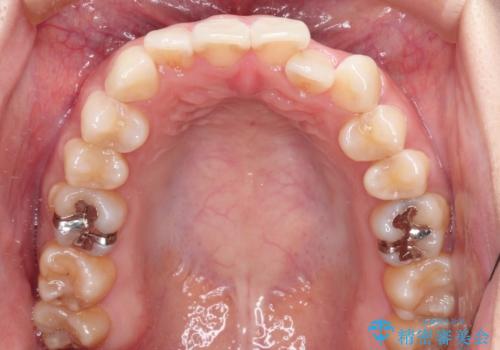

前歯のがたつきと反対咬合 インビザラインによる矯正治療

- 前歯のがたつきと反対咬合を主訴に来院されました。

下の前歯のがたつきを改善するために、右下の奥歯を後方に移動させるのと、歯と歯の間をわずかに削り、歯を並べる計画としました。

前歯の正中のずれを修正するのに少し時間がかかりましたが、整った歯並びにすることができました。